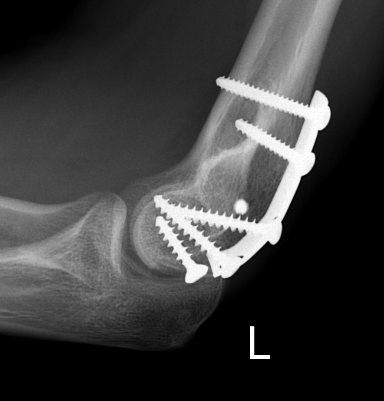

Fixation

Headless compression screws AP / PA

Lateral approach and ORIF

Technique

Arm on side table with tourniquet

- lateral approach centered on lateral epicondyle

- split extensor muscle

- open capsule and identify capitellum fracture

- reduce fracture

Usually AP headless compression screws (violates articular surface)

- +/- PA screws (risk AVN)

- +/- postero-lateral plate

ORIF with AP screws

ORIF Type II with screws